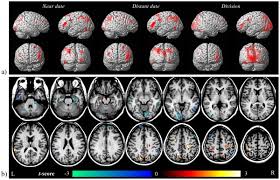

The Connectomes Of Males And Females With Autism Spectrum Disorder Have Significantly Different White Matter Connectivity Densities Scientific Reports

The Connectomes Of Males And Females With Autism Spectrum Disorder Have Significantly Different White Matter Connectivity Densities Scientific Reports from media.springernature.com

Many of the institutes at the nih, including the ninds, are sponsoring research to one study is using functional magnetic resonance imaging (fmri) to show how abnormalities in particular areas of the brain cause changes. Standing at the bottom of the stairs that led up to his son's room, he voiced…adam, it's time to leave for school. asperger syndrome 3. Asperger syndrome and other terms // the national autistic society. Deep brain stimulation in epilepsy with particular reference to the subthalamic nucleus. The first account of the syndrome asperger described? Come into use until several decades later when wing (4). Now it is identified as one form of the autism spectrum disorder diagnosis people diagnosed with asperger's syndrome typically have high intelligence and no speech delays. Asperger's syndrome is part of a related group of brain disorders called autism spectrum disorders (asds).